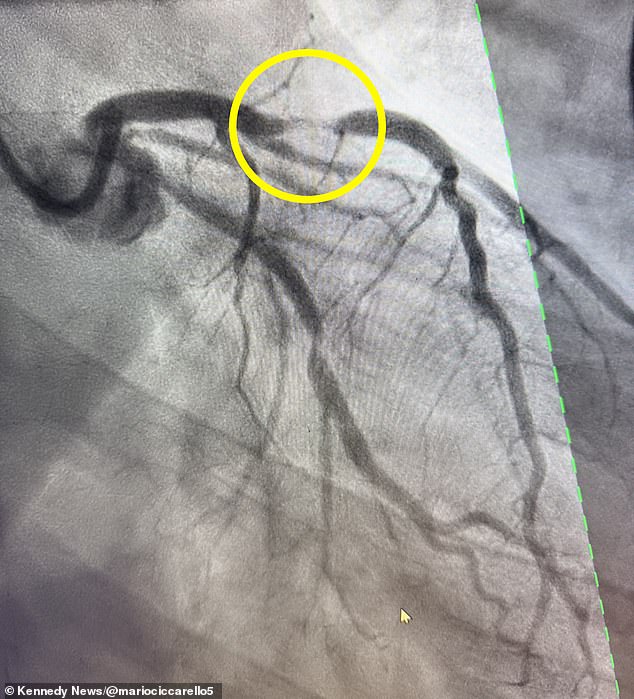

Ciccarello and James rushed to the hospital, where doctors found he had suffered a 95 percent blockage in his left anterior descending (LAD) artery, which supplies more than half of the heart’s blood.

The blockage causes a ‘widow-maker’ heart attack, a name that refers to the high mortality rate.

Despite low odds, doctors were able to save Ciccarello’s life by inserting two stents – mesh tubes that restore blood flow through blocked arteries – into his heart.